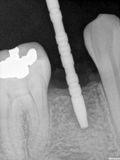

fredlibc | all galleries >> Galleries >> WYu - 44 implant > R1.jpg

R1.jpg